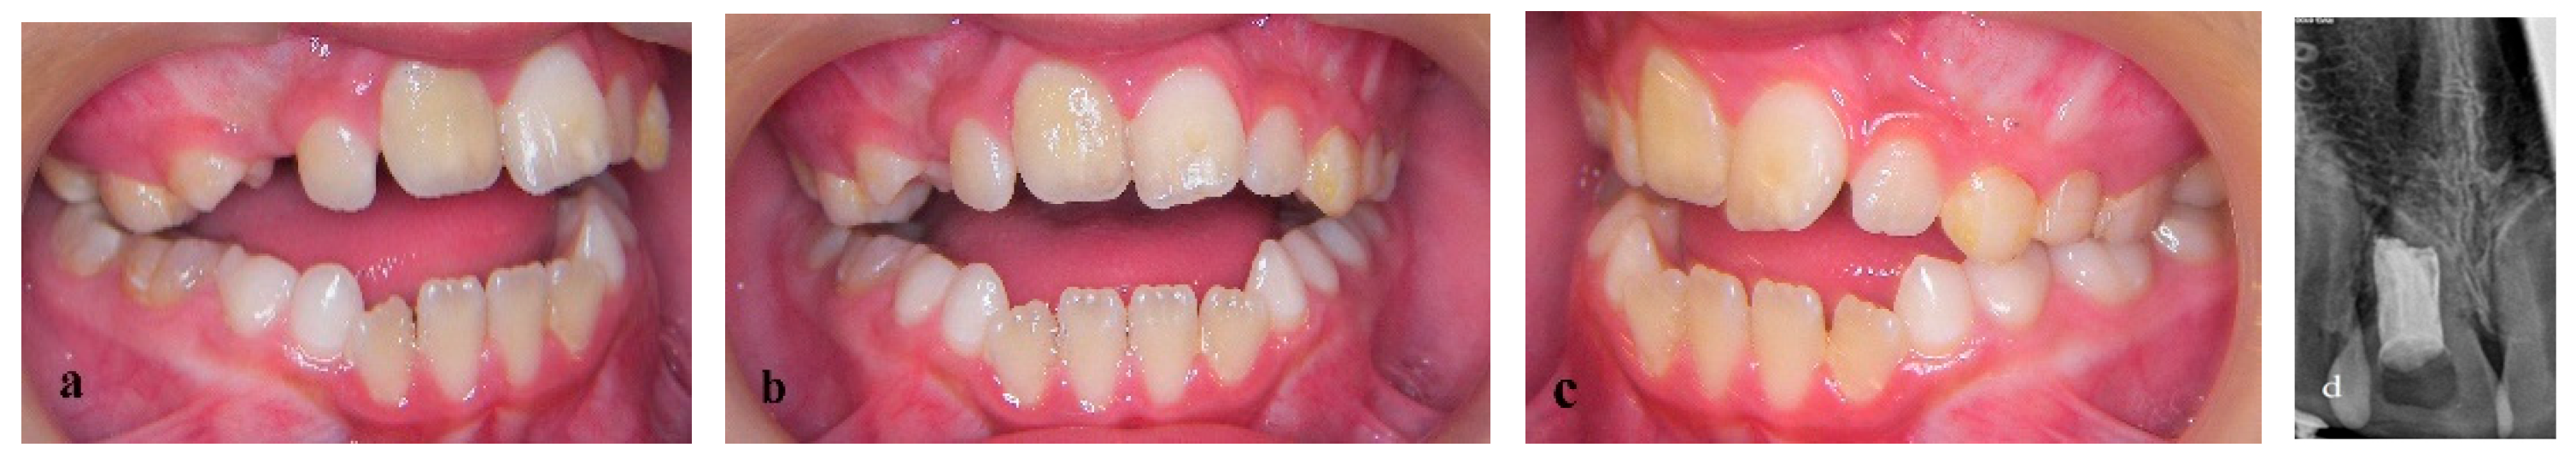

Treatment of an Avulsed and Ankylosed Incisor through Single Tooth Alveolar Osteotomy and Conventional Orthodontic Mechanisms

2. Materials and Methods

3. Results